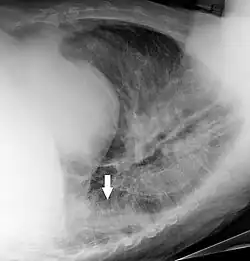

In projectional radiography, visual artifacts that can constitute disease mimics include jewelry, clothes and skin folds.[7]

A hip fracture (black arrow) next to a skin fold (white arrow) -

Bed sheets looking like lung opacities on a chest radiograph